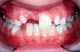

Vorstehende Schneidezähne. Wenn die Schneidezähne sehr weit vorstehen, sind besonders sie gefährdet. Ungefähr die Hälfte aller Kinder verletzen sich die Zähne bei Stürzen und Unfällen. Fragen Sie Ihren Kieferorthopäden, wann eine Behandlung begonnen werden sollte.